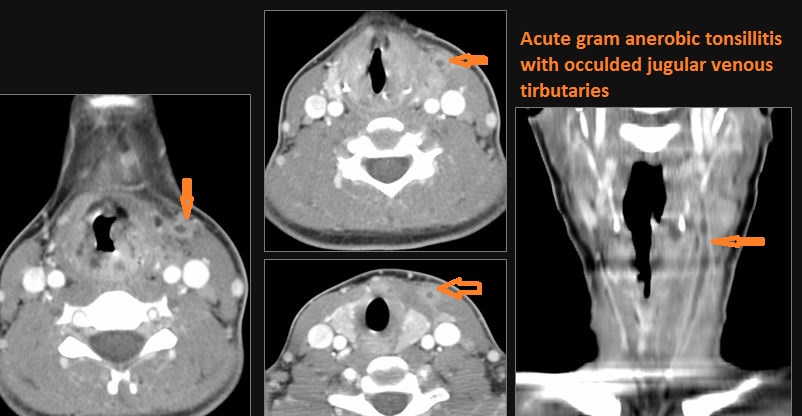

1-year old with fever, difficulties feeding and possible retropharyngeal abscess.Exam

Contrast-enhanced CT of the maxillofacial region and neck and related anatomy with images obtained in the balanced or venous vascular phase to ensure optimal visualization of both arterial and venous structures as well as possible reactive changes around infected collections. 0.5-3.0 mm thick sections were obtained in the axial plane and reformatted 3D and/or in the coronal and sagittal planes and viewed inter actively in 3 dimensions at the computer work station.